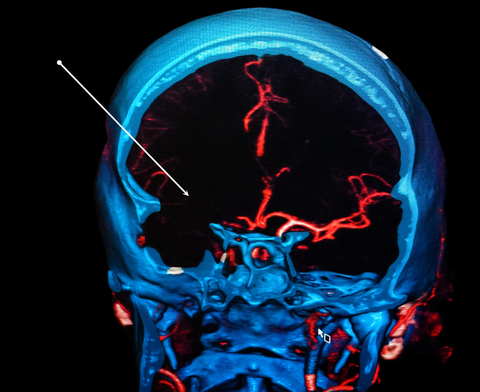

Contributor: Aaron Lessen, MD Educational Pearls: The cause of Alzheimer's disease is multifactorial, but the most widely suspected mechanism is the amyloid cascade hypothesis: Beta-amyloid proteins accumulate in the central nervous system, forming plaques that impair neuronal function. In recent years, advances have led to the development of targeted therapies with monoclonal antibodies. These drugs: Work by degrading amyloid plaques Slow the rate of cognitive decline and disease progression Have major side effects, most notably the development of amyloid-related imaging abnormalities (ARIA) ARIA may present as edema, effusion, or microhemorrhages, which are only detectable on MRI Symptoms can include headache, vertigo, or focal neurologic deficits that mimic stroke For patients presenting to the emergency department with stroke-like symptoms, it is important to consider whether they have a history of Alzheimer's disease and whether they are taking these medications. This guides decisions about imaging and treatment: The work-up may require MRI, which can delay thrombolytic or endovascular therapy in patients with true strokeConversely, treating a patient with ARIA using thrombolytics increases the risk of bleeding and other complications References Ebell MH, Barry HC, Baduni K, Grasso G. Clinically Important Benefits and Harms of Monoclonal Antibodies Targeting Amyloid for the Treatment of Alzheimer Disease: A Systematic Review and Meta-Analysis. Ann Fam Med. 2024 Jan-Feb;22(1):50-62. doi: 10.1370/afm.3050. PMID: 38253509; PMCID: PMC11233076. Ma C, Hong F, Yang S. Amyloidosis in Alzheimer's Disease: Pathogeny, Etiology, and Related Therapeutic Directions. Molecules. 2022 Feb 11;27(4):1210. doi: 10.3390/molecules27041210. PMID: 35209007; PMCID: PMC8876037. Perneczky R, Dom G, Chan A, Falkai P, Bassetti C. Anti-amyloid antibody treatments for Alzheimer's disease. Eur J Neurol. 2024 Feb;31(2):e16049. doi: 10.1111/ene.16049. Epub 2023 Sep 11. PMID: 37697714; PMCID: PMC11235913. Summarized by Ashley Lyons, OMS3 | Edited by Ashley Lyons and Jorge Chalit, OMS4 Donate: https://emergencymedicalminute.org/donate/